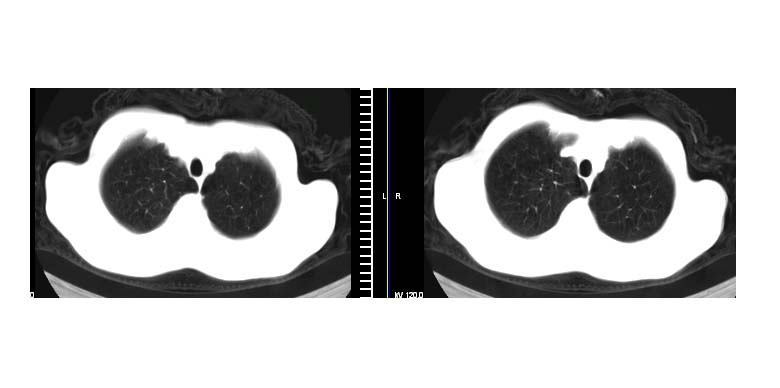

标题: CT11019:男性,66岁。发烧5-6天。治疗后无明显好转。 [打印本页]

标题: CT11019:男性,66岁。发烧5-6天。治疗后无明显好转。

左下肺中央型肺癌伴阻塞性肺炎\\肺不张可能性大,建议支纤镜检查.

1.左肺门似可见一小块影,由此考虑中央型肺ca并阻塞性肺炎改变;

2.左下叶背段肺tb(干酪性肺炎)?

3.单纯肺感染?建议进一步检查。

左下肺中心性肺癌伴下肺不张及周围阻塞性炎症

左下肺中央型肺癌伴阻塞性肺炎\\肺不张可能性大,建议支纤镜检查

左肺门下分增大见有结节影,基底干及分支显示不清,下叶体积缩小,呈片带状机磨玻璃样影显示。支持考虑左下肺中心型肺癌伴阻塞性肺炎及部分肺不张。建议纤支镜检查